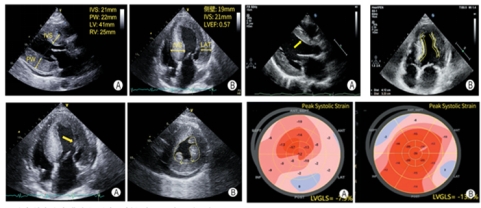

数月前一个炎热的下午,一名中年女性步入心脏超声诊室,她因反复胸闷不适来我院就诊,心脏影像中心主治医师吴丽苹在进行超声检查时,发现患者心脏室壁对称性异常增厚、乳头肌肥大、心肌内膜回声偏亮,而患者并无高血压糖尿病等基础疾病。此时一个想法在脑海里油然而生,患者的超声表现可能与罕见病“法布雷病”有一定相关,随即对患者进行斑点追踪显像技术测量,结果与预想的一致。

《中国法布雷病超声心动图规范化筛查指南(2024版)》指出法布雷病心脏受累的典型超声心动图表现包括:左心室向心性肥厚、“双边征”、乳头肌不成比例肥大、右心室肥厚并具有正常收缩功能、左心室舒张功能异常、下外侧壁基底段纵向应变减低。